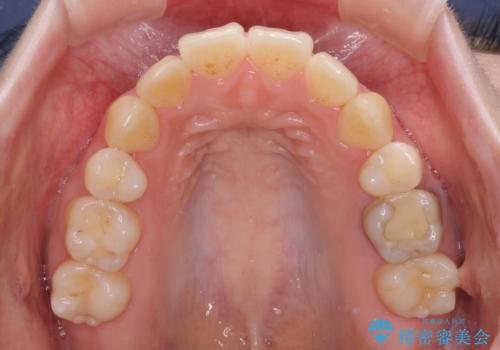

- 高校生の時に矯正治療を行ったものの、後取りをしてしまったとのことで来院された患者様です。

マウスピースでもワイヤー矯正でも対応可能でしたが、再度ワイヤーは装着したくないとのことでインビザラインにて矯正治療を行うこととしました。

舌の突出癖が原因で後戻りをしたため、舌のトレーニングをしっかりと行っていただき、口元の突出感を改善することができました。